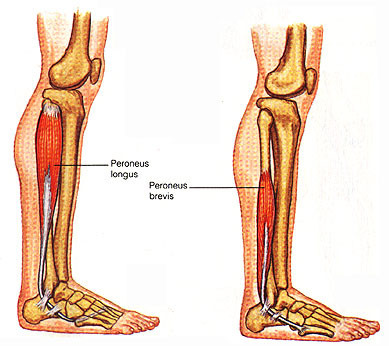

- peroneus longus and brevis 안정화 운동, 근력강화운동

재활 후 발 아치가 무너지는 것을 막아야